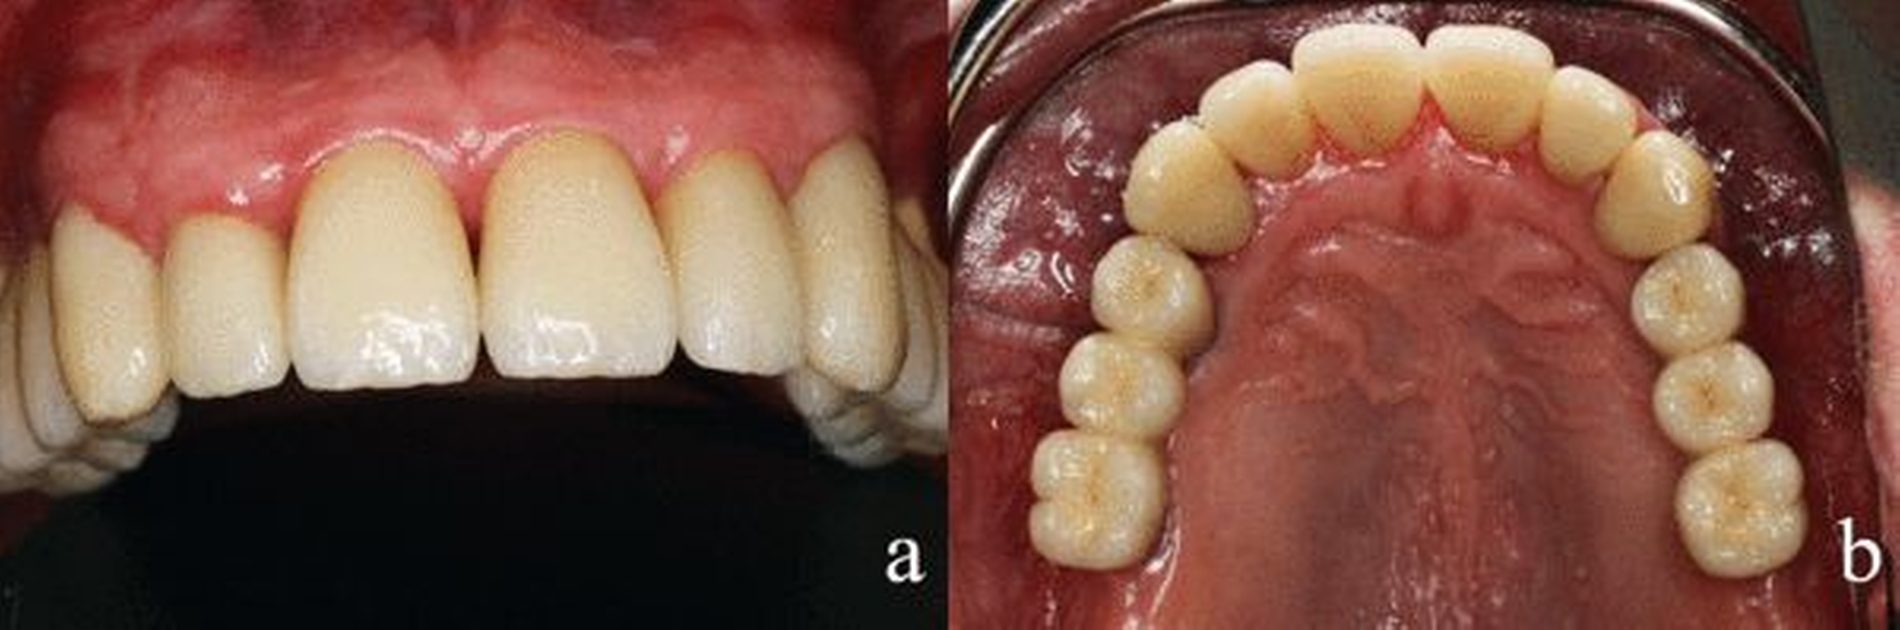

Der autologe Knochen wurde aus der Linea obliqua mandibulae Regio 38 und 48 entnommen und in Regio 14, 24, 34 und 44 zur Knochenverbreiterung eingebracht (Abbildungen 4a und b). In Regio 16 und 26 erfolgte zudem ein externer Sinuslift zur Knochenerhöhung. Simultan wurden Implantate Regio 16, 26, 36, 44 und 46 inseriert. Drei Monate später wurden diese Implantate freigelegt und Regio 14, 24 und 34 weitere Implantate eingesetzt (Abbildungen 5a-c). Nach weiteren drei Monaten erfolgte die Implantatfreilegung Regio 14, 24 und 34 und die prothetische Gesamtversorgung (Abbildungen 6a und b).

Der Patient stellte sich regelmäßig zu Nachkontrollen vor. Es wurden Termine zur professionellen Zahnreinigung in halbjährlichen Intervallen vereinbart. Zurzeit des hier vorgelegten Berichts lag der Behandlungsabschluss sieben Jahre zurück (Abbildungen 7 und 8a-c).

Besonders der kollegiale Austausch kann in solch einem Fall dazu Beitragen, die von dem behandelnden Zahnarzt ausgehenden vorschnellen Urteile über Persönlichkeit und Verhalten eines Patienten abzuwehren und so eine systematische und strukturierte Therapieentscheidung zu finden. Aufgrund der guten Compliance sowie der deutlichen Verbesserung der Mundhygiene entschieden wir uns für den Zahnerhalt im Frontzahnbereich und eine implantologische Lösung im Seitenzahnbereich. Das zahnärztliche Ziel war, den Patienten nach aufwendiger Rekonstruktion über viele Jahre zu guter Mund-hygiene zu motivieren. Dies konnte durch intensive Aufklärung erreicht werden. Bereits nach den ersten Maßnahmen zeigte sich eine deutliche Besserung der Mundgesundheit. Der Patient begann darauf zu vertrauen, dass eine ihm adäquate Therapie erfolgte. Er entwickelte bald ein gesteigertes Selbstwertgefühl. Schon nach Eingliederung des Provisoriums verbarg er die Zähne nicht mehr hinter den Lippen und gewann sein Lächeln zurück. Seine Gesprächsbereitschaft steigerte sich deutlich. Die Versorgung ist auch nach sieben Jahren stabil (Abbildungen 7, 8a-c). Außer den regelmäßigen professionellen Zahnreinigungen waren keine zahnärztlichen Eingriffe erforderlich. Lediglich ein Chipping der Keramik Regio 46 ist anzumerken. Dies hatte jedoch funktionell und ästhetisch für den Patienten keine Auswirkung.